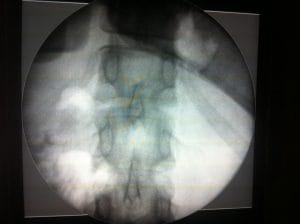

During your consultation for Bariatric Surgery for Morbidly Obese, Prof Wilson will discuss its limitations and risks, and your needs and concerns. He will explain how to make your stomach smaller, so that you will feel satisfied after a small meal. He will advise you on the dietary regulation after the surgery so that you can get all your nutritional needs from a small meal. Dr. Wilson will also advise you on the follow up protocol. Depending on the quality of your skin tone and the contour of your body, he will discuss the possibility of carrying out a body lift after your weight stabilizes.

Although with modern techniques, the complications of surgery are markedly reduced, this still remains a major surgical procedure. Risks include dislodgement of the gastric band, anastomotic leakage, and failure to lose weight. A Dietitian carefully monitors the nutrition of patients who lose weight to avoid malnutritional problems.